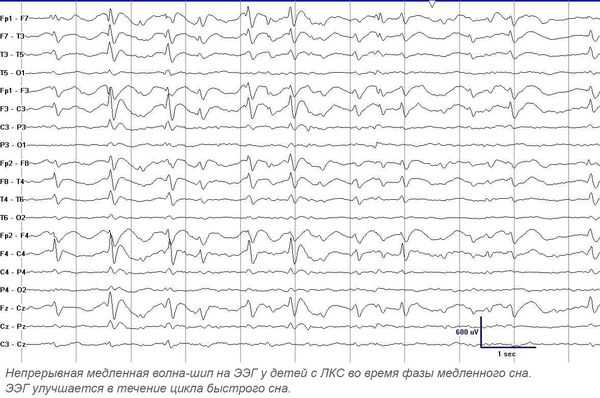

Основной метод диагностики — электроэнцефалография (ЭЭГ). Повышенная эпилептиформная активность может быть подтверждена длительным ЭЭГ видео-мониторингом (суточным или ночным). Эпилептиформная активность представляет собой электрические колебания головного мозга в виде острых волн и пиков. Она значительно (более чем на 50 %) отличается от фоновой активности и, как правило, обнаруживается на ЭЭГ у лиц, страдающих эпилепсией. Ночной мониторинг выполняется в виде непрерывной регистрации электроэнцефалограммы в течение ночи. При ЛКС в период сна происходит увеличение патологической активности — появление непрерывного всплеска и пик-волновой активности во время медленного сна, в основном с частотой 1,5-2,5 Гц. В 70-80 % случаев ЛКС сопровождают моторные эпилептические припадки.

При проведении ЭЭГ у всех больных выявляют эпилептиформные изменения. Патогномоничны высокие пик-волны, регистрируемые в височных областях и наиболее выраженные в фазу медленного сна. Последнее диктует необходимость проведения ЭЭГ сна, которая зачастую регистрирует электрический эпилептический статус медленного сна — постоянную диффузную эпилептическую активность в период медленноволнового сна. При отсутствии изменении на ЭЭГ сна рекомендуется длительное ЭЭГ-мониторирование.